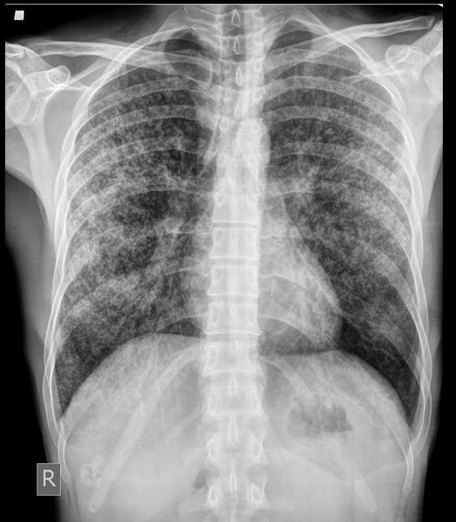

Miliary Tuberculosis/TB milier adalah bentuk tuberculosis yang lumayan parah, di mana bakteri TB menyebar lewat darah dan sistem limfa ke seluruh tubuh.

Salah satu gejalanya adalah munculnya benjolan-benjolan kecil sebesar 1-3 mm yang tersebar ke seluruh tubuh.

Untuk diagnosis, dokter biasanya melakukan rangkaian pemeriksaan yang cukup lengkap mulai dari pemeriksaan fisik, foto thorax, tes dahak, sampai tes darah.